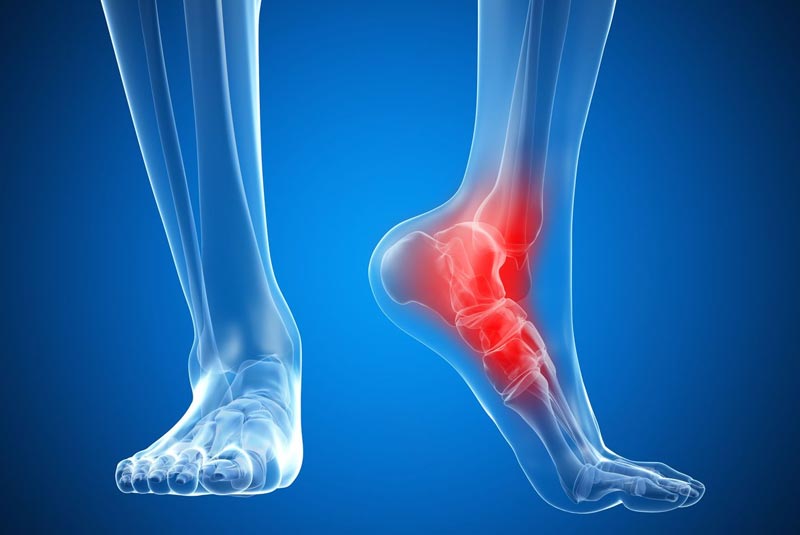

Έχει 5ετή μετεκπαίδευση και εργασία στο Ηνωμένο Βασίλειο ως ειδικός Ορθοπαιδικός Χειρουργός. Έχει εργαστεί στα Ορθοπαιδικά Τμήματα των Νοσοκομείων Southampton University Hospitals NHS Trust, Leeds Teaching Hospitals NHS Trust και στο Northampton General Hospital NHS Trust, με υποεξειδίκευση στη Χειρουργική Ώμου, Γόνατος, Ισχίου, Ποδοκνημικής & Άκρου Ποδός, Ώμου & Αγκώνος και Γενικού Τραύματος Ενηλίκων και Παίδων.

Κατά τη διάρκεια της εργασίας του στο Ηνωμένο Βασίλειο εκπαιδεύτηκε σε σύγχρονες τεχνικές Αρθροσκοπικής Χειρουργικής και Επανορθωτικής Χειρουργικής Ισχίου, Γόνατος και Ώμου. Επιπλέον έχει δώσει πολυάριθμες διαλέξεις και έχει εκπαιδεύσει νεότερους Ορθοπαιδικούς και φοιτητές Ιατρικής. Αξιοσημείωτο και πλούσιο είναι το επιστημονικό του έργο με συμμετοχή σε δεκάδες συνέδρια και σεμινάρια στην Ελλάδα και στο εξωτερικό και έχει πληθώρα προφορικών ανακοινώσεων και δημοσιεύσεων.